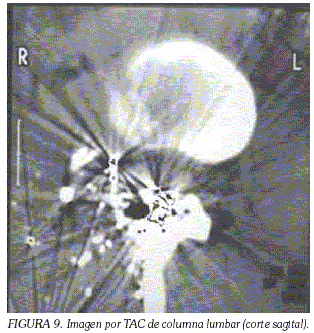

Otro tipo de lesiones frecuentes en las heridas por armas de baja velocidad son las lesiones intrarraquídeas por fragmentos o por esquirlas, producto de la fragmentación secundaria de estos proyectiles al impactar sobre las estructuras óseas, causando lesiones radiculares, como la que se observa en la figura 9.

c. Lesiones por armas de fragmentación no convencionales.